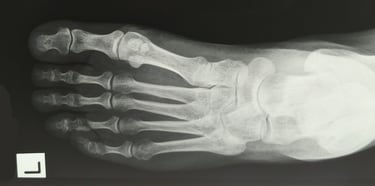

Foot